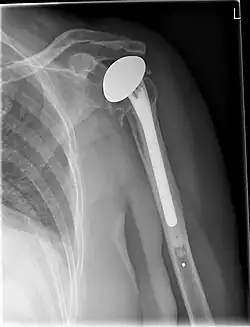

Kunstgewrichten worden toegepast voor heupen, knieën, schouders,ellebogen enkels en polsen.

Kunstheupen zijn zeer succesvol, gevolgd door knieën, maar ook vervangende kunstschouders, -enkels en -polsen winnen terrein. In de rug worden ook versleten of beschadigde (tussen)wervelschijven meer en meer vervangen, maar door de vele zenuwbanen en dergelijke is dat niet zonder risico.